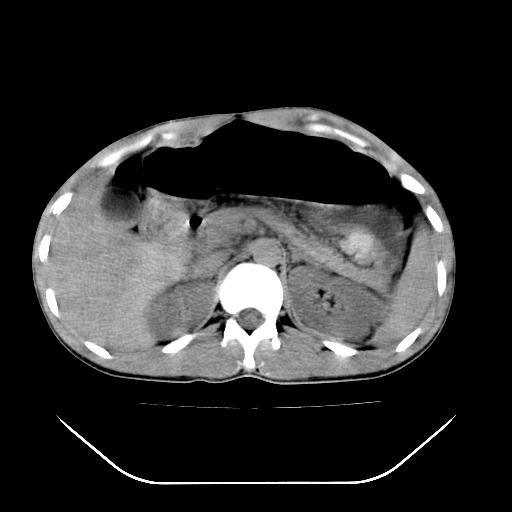

除了1:左肾挫裂伤并肾周血肿;

2:少量腹水

第二次ct检查后:临床医生腹水穿刺后考虑肠系膜动脉破裂,后实行剖腹探查:于空肠距离十二指肠90cm处发现肠管破裂,破裂口较小;修补后关腹。

顺便请各位老师认真看看7号片

各位老师觉得胆囊是不是有点积血。我在原始片看胆囊密度不均,似有小液平面

再有就是支持楼主,胆囊7日片比5日片不仅增大许多,靠后下更见液液分层,应该是有积血。

结果收到,谢谢楼主,另外反过来看这个地方是不是游离气体影